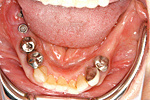

症例 10

① 右上奥歯がありません。普通なら取り外しの顎つき入れ歯しか入りません。

② インプラントしたことで固定式の自分の歯に近い義歯が入りました。

50才代 女性

総額:170万円(税別)

治療期間:6ヵ月

リスク副作用:ブラッシング不良によるインプラント周囲炎の発生。